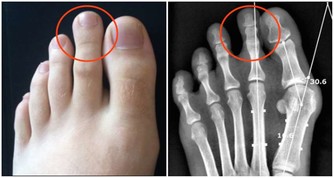

林明恩醫師進一步說明,美國哈佛大學在1999年研究指出,約占一半的大腸直腸癌患者,診斷時都有貧血症狀,且2005年英國報告也顯示,容易貧血的人罹患大腸直腸癌機率比一般人高出2至3倍,另外,包括胃癌、食道癌、血液腫瘤等消化道惡性腫瘤,都有可能在被確診前,就先出現貧血的現象,不得輕忽嚴重性。